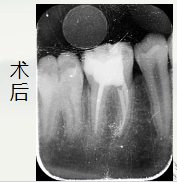

这里使用的是

松风纳米树脂 beautifil II A2色树脂

术后讨论:

牙冠修复:根管治疗后的牙齿失去牙髓营养供应,容易变脆。建议完成治疗

后做牙冠保护,但由于孩子还在生长发育,牙弓和颌骨可能会变化。我们可

能会先做一个预成冠(不锈钢牙冠)来暂时保护牙齿,它坚固耐用且经济。